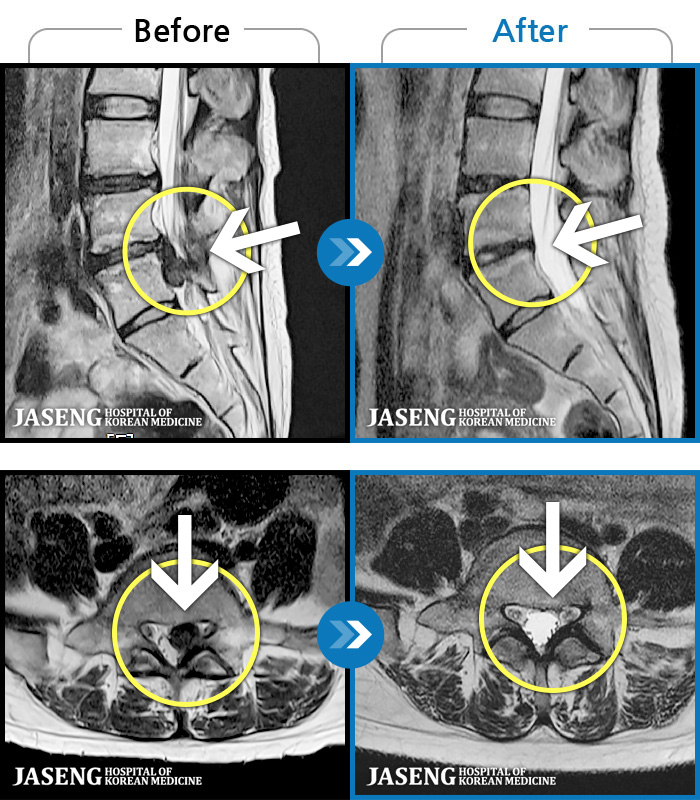

1,228건의 MRI 전후 사진으로 터진 디스크 흡수 사례를 확인하세요.

※ 환자분에게 사전 동의를 받아 동일 조건에서 촬영되었으며, 개인에 따라 치료 후 부작용이 발생할 수도 있으니 사전에 의료진과 상담 후 치료를 진행하시기 바랍니다.